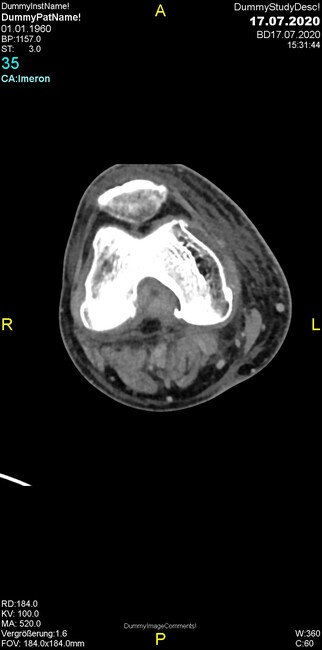

Um welche Modalitäten handelt es sich?

- Röntgen p.a. und lateral, CT coronar Knochenfenster, CT axial Weichgewebsfenster

- Röntgen p.a. und oblique, CT coronar Knochenfenster, CT axial Weichgewebsfenster

- Röntgen p.a. und lateral, CT sagittal Weichgewebsfenster, CT coronar Knochenfenster

- Röntgen p.a. und oblique, CT sagittal Knochenfenster, CT coronar Weichgewebsfenster

- Röntgen p.a. und lateral, CT coronar Weichgewebsfenster, MR axial

Was fällt in der CT im Knochenfenster auf?

- Mediale Gelenkspaltverschmälerung

- Dezente Erosion der fibulären Kortikalis

- Frakturspalt der lateralen Tibiametaphyse

- Weichgewebskalzifikationen lateral angrenzend an den Gelenkspalt

- Osteolyse der Tibiametaphyse unter Beteiligung der Kortikalis